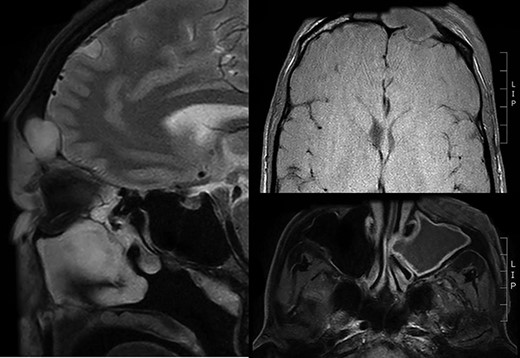

A 34-year-old gentleman presented to the emergency department of a regional hospital with 2 days of left-sided periorbital swelling superior to the eye socket with associated erythema and tenderness. He was assessed to have normal visual acuity and extraocular movements. He had a history of severe ankylosing spondylitis for which he was taking a TNF inhibitor, adalimumab. His blood tests showed a slightly raised C-reactive protein of 82 mg/l but otherwise no abnormality. Magnetic resonance imaging (MRI) was performed on the day of admission and noted significant left frontal sinusitis complicated by a defect of the frontal cortical bone as well as oedema and enhancement consistent with a Pott’s puffy tumour (Fig. 1). There was also an abscess of the periorbital soft tissue. Immediate treatment was given in the form of phenylephrine nasal decongestants and intravenous antibiotics (amoxicillin with clavulanic acid), and the patient was transferred to a tertiary centre with ear, nose and throat surgery capacity.